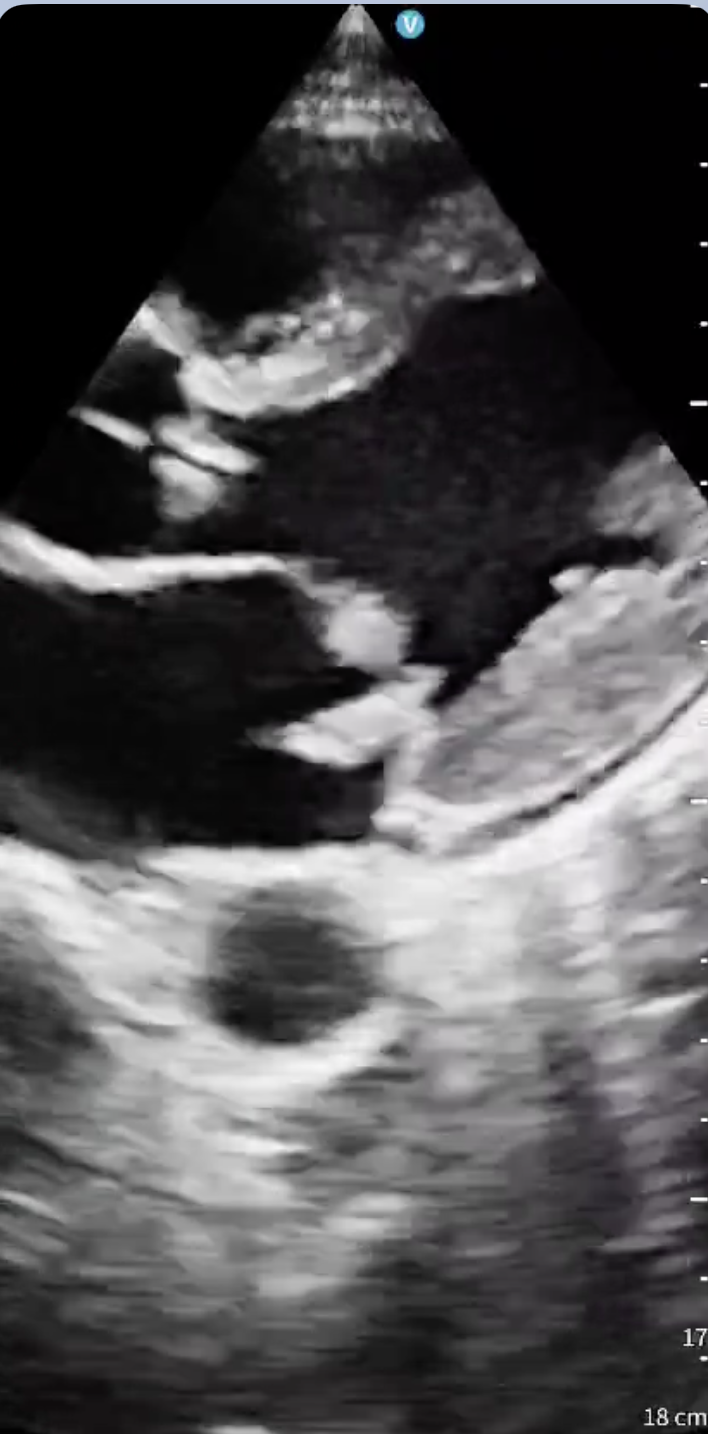

Hombre de 38 años, consumidor de múltiples sustancias, trasladado a Urgencias tras hallarse en vía pública con bajo nivel de conciencia, fiebre y taquicardia. Presenta Glasgow 9, orientación conservada pero obnubilación, y auscultación cardiopulmonar anodina. La analítica sanguínea evidencia leucocitosis con neutrofilia, elevación de proteína C reactiva, procalcitonina y troponina I ultrasensible. Las serologías son positivas para virus de la inmunodeficiencia humana y hepatitis C, y el cribado toxicológico para cannabis y cocaína. Durante la estancia en Urgencias empeora neurológicamente, realizándose tomografía cerebral que muestra ictus isquémico en territorio de la arteria cerebral posterior derecha. Dados los antecedentes, la primera sospecha es la de origen cardioembólico, así que se realiza ecocardiografía clínica a pie de cama, objetivándose válvula mitral con velos engrosados y gran vegetación de 5×8 milímetros que prolapsa hacia aurícula generando insuficiencia mitral severa. Se observa además válvula aórtica trivalva engrosada con vegetaciones en todos los velos, compatible con endocarditis infecciosa.

En un paciente febril, consumidor de tóxicos y con deterioro del nivel de conciencia, se plantea diagnóstico diferencial entre sepsis de origen no filiado, infección del sistema nervioso central, intoxicación aguda e infarto cerebral. Tras el resultado de la tomografía, la cardiopatía estructural embólica pasa a ser la primera causa a descartar. El hallazgo ecográfico resulta determinante para identificar el origen cardioembólico y orientar el cuadro como endocarditis infecciosa complicada con embolización cerebral.